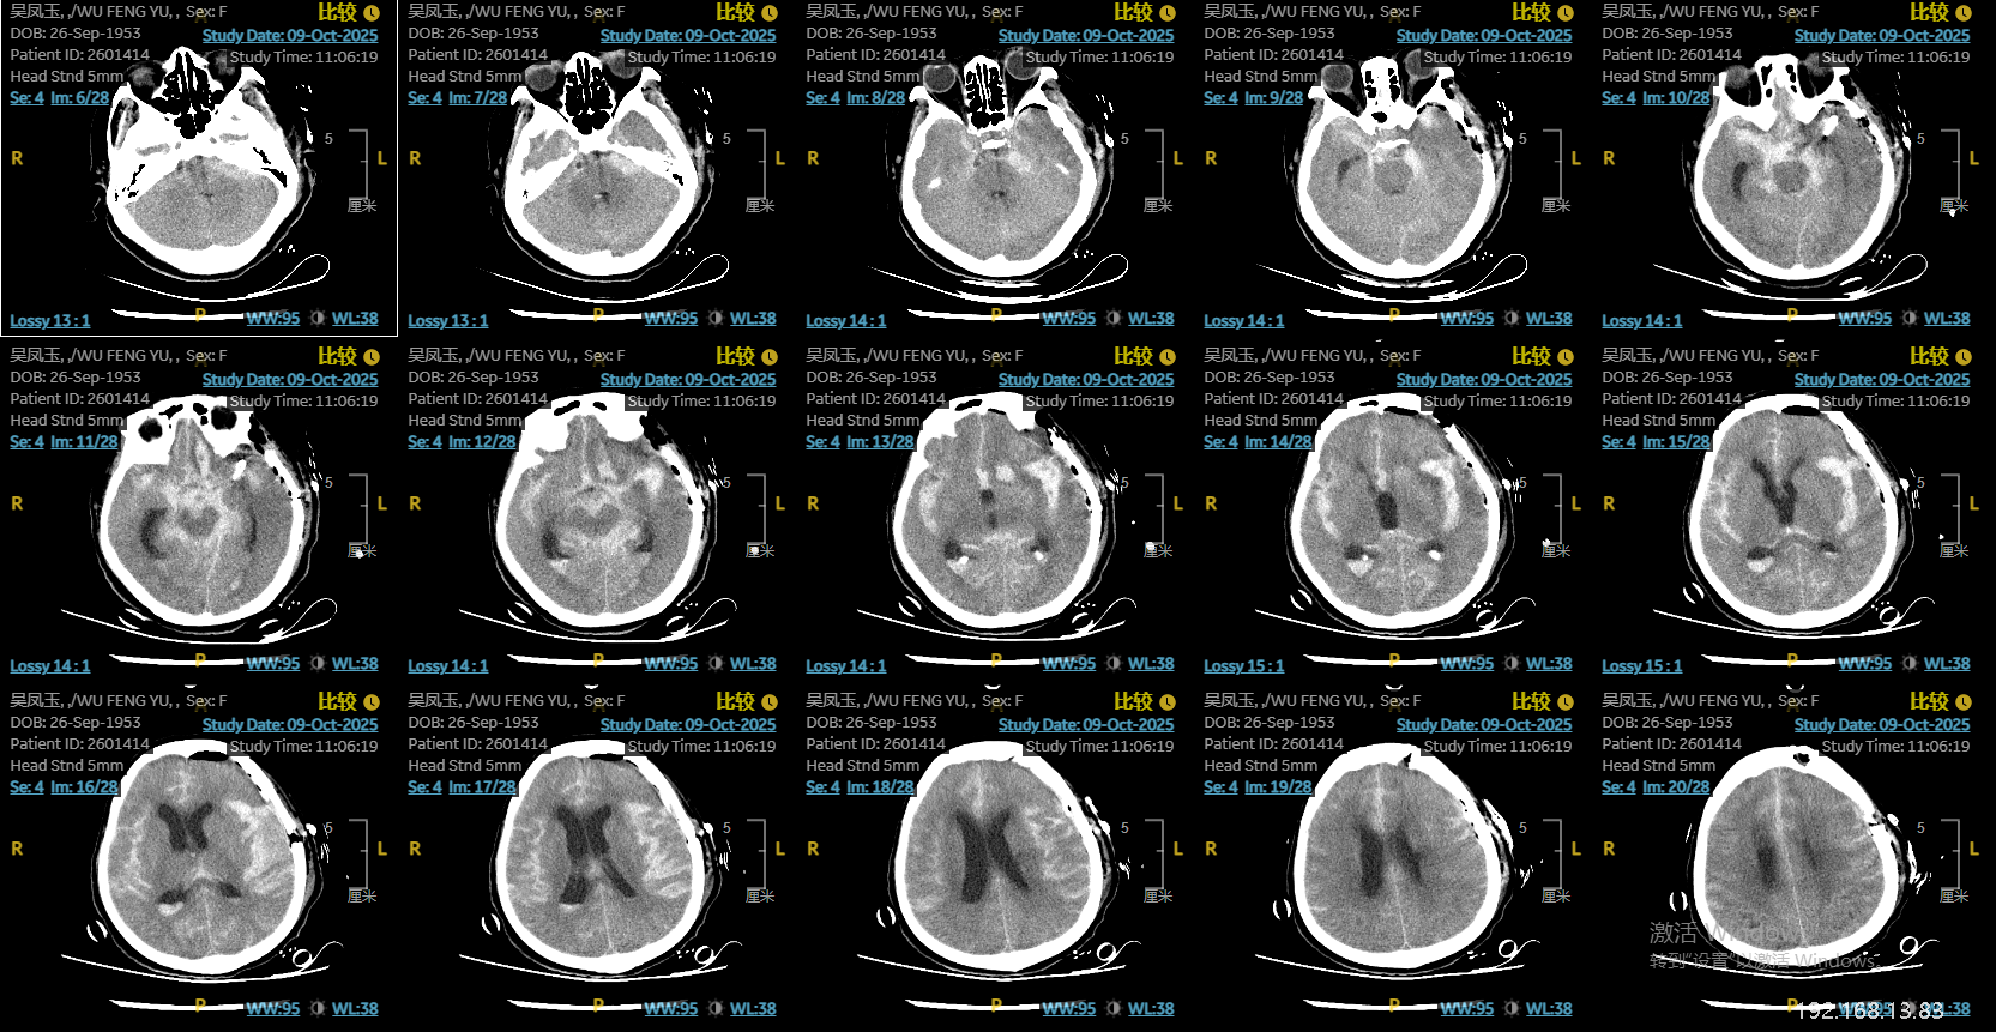

患者老年女性,72岁,昏迷入院。